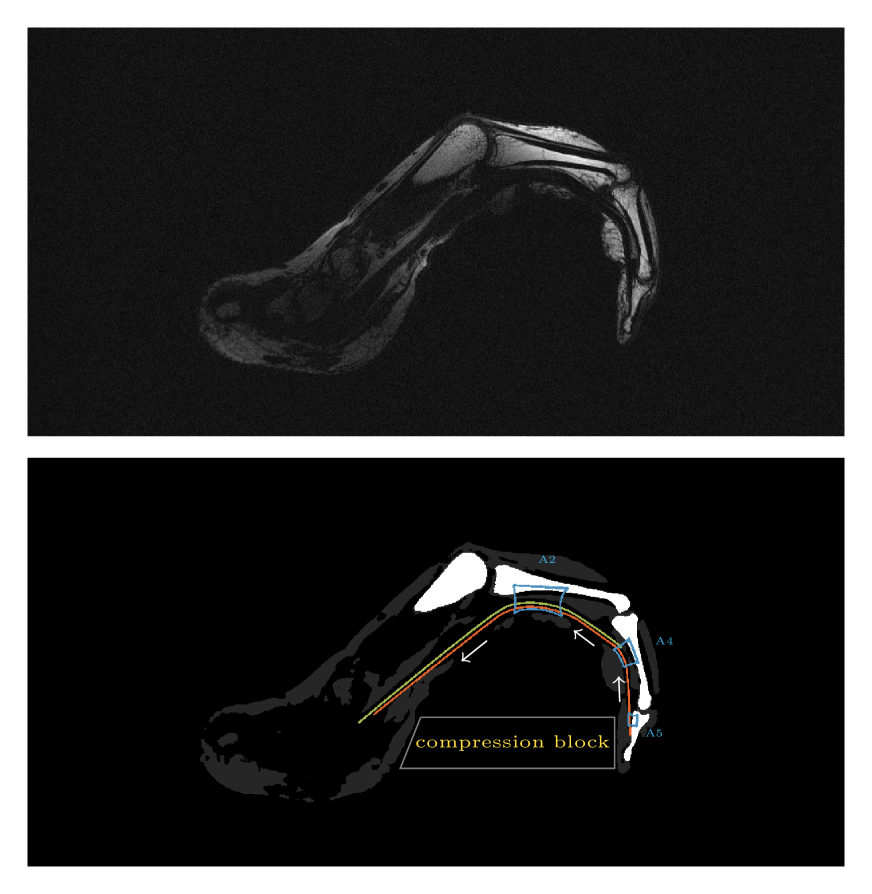

[Uncaptioned image]

Supplemental Figure 5: Sagittal T1 weighted image through the flexor tendon in the index finger while squeezing a block of wood (top penal). Although pulley ligaments and flexor tendon are almost indistinguishable based on underlying contrast (both have short T2 relaxation times), their interaction can now be revealed. As the subject squeezes on the compression block, the load on the flexor tendon is distributed over the pulleys as illustrated in the bottom panel.